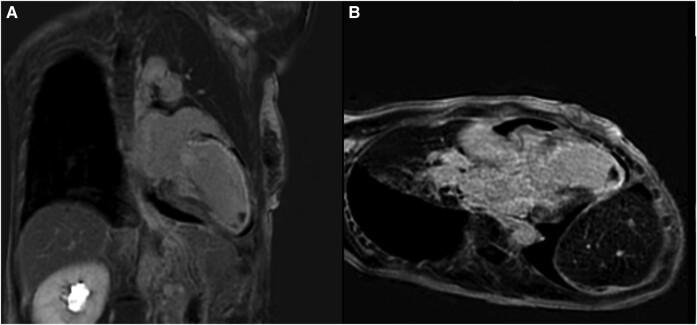

A previously healthy 39-year-old woman experienced sudden severe chest pain, ST-segment elevation on electrocardiogram, necessitating high-dose aspirin and urgent transfer to a revascularization centre. Suffering ventricular tachycardia (VT) and ventricular fibrillation (VF), she underwent two rounds of advanced life support and venoarterial extracorporeal membrane oxygenation. Diagnosed with left main coronary artery (LMCA) SCAD, she was initially started on conservative therapy for declining left ventricular ejection fraction. However, she continued to experience an escalating anginal symptoms, worsening biomarkers, and LMCA SCAD progression, which urged the need for surgical intervention with coronary artery bypass graft surgery (CABG). Following her CABG, she experienced a worsening of her functional mitral regurgitating, which she underwent transcatheter edge-to-edge repair of her severe mitral regurgitation. Despite being listed for orthotopic heart transplantation (OHTx), her low body mass index and elevated antibodies necessitated the HeartMate III left ventricular assist device (LVAD) for bridge to transplant. After treating frequent VT episodes with medications, she eventually received a LVAD as a bridge to cardiac transplantation. Within 1 year of her receiving LVAD, she underwent a successful OHTx.

一名既往健康的39岁女性突发严重胸痛,心电图显示ST段抬高,需要大剂量阿司匹林治疗并紧急转至血管重建中心。她出现室性心动过速(VT)和室颤(VF),接受了两轮高级生命支持和静脉-动脉体外膜肺氧合治疗。诊断为左主干冠状动脉(LMCA)SCAD,最初因左心室射血分数下降开始接受保守治疗。然而,她持续出现心绞痛症状加重、生物标志物恶化以及LMCA SCAD进展,这促使需要进行冠状动脉旁路移植术(CABG)手术干预。CABG术后,她的功能性二尖瓣反流恶化,因此接受了经导管二尖瓣缘对缘修复术治疗严重二尖瓣反流。尽管被列入原位心脏移植(OHTx)名单,但她的低体重指数和抗体升高使得需要使用HeartMate III左心室辅助装置(LVAD)作为移植桥梁。在用药物治疗频繁发作的VT后,她最终接受了LVAD作为心脏移植的桥梁。在接受LVAD的1年内,她成功接受了OHTx。